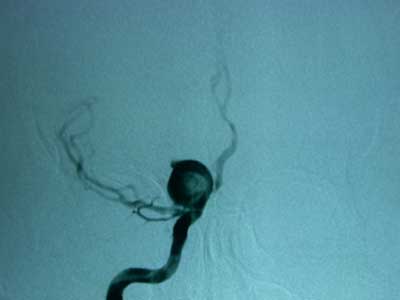

Fig. 11A.- Angiografía antes de

colocación clip

Fig. 11B.- Angiografía antes de